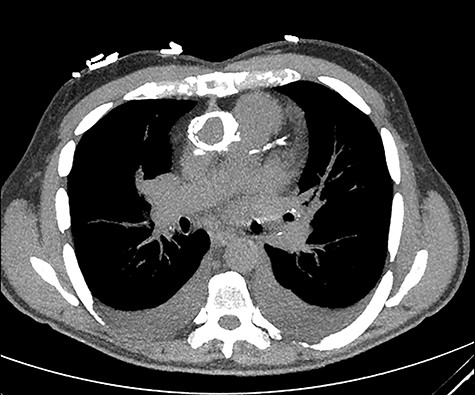

The aortic homograft was circumferentially calcified as shown by a preoperative chest computed tomography scan.

The aortic homograft was circumferentially calcified as shown by a preoperative chest computer tomography scan (Fig. 2). In addition to the extensiveness of the previous operation, severe adhesions around the heart were expected; therefore, a right mini-thoracotomy approach was used. A right anterolateral thoracotomy with a small incision was performed at the fifth intercostal space under single lung ventilation. Cardiopulmonary bypass (CPB) was initiated with the right femoral artery and vein cannulations. Prior to the start of the procedure, an EndoVent™ Pulmonary Catheter (8.3Fr; Edwards Lifesciences, Irvine, CA) was also placed percutaneously through the right internal jugular vein by the anesthesiologist and drained at ~500 ml/min during the CPB. The pericardium was opened, and minimum adhesions were found on the right side of the heart due to the incision of the previous MVR located at the left atrial dome. The right side of the left atrium was dissected, and the right atrium was partially dissected along with the right pulmonary veins. At this point, the patient was cooled down to 30°C for ventricular fibrillation. Once the patient began fibrillating, the left atrium was opened. The mechanical prosthesis was largely detached. The valve was thus duly excised and the annulus was debrided. Interrupted 2–0 Ethibond mattress sutures with pledgets and a 29-mm Mosaic™ mitral valve (Medtronic, Minneapolis, MN) was placed. The left atriotomy was then closed with 2–0 running sutures of 3–0 Prolene around the vent tube that was placed in the left ventricle through the prosthesis. With the patient in the reverse Trendelenburg position and the left side down, the patient was defibrillated. Although the prosthesis was incompetent, the heart was allowed to eject air. After adequate de-airing as confirmed by intraoperative transesophageal echocardiography, the vent tube was removed and the atriotomy was completely closed. CPB was weaned off uneventfully. The ventricular fibrillatory arrest time was 103 min and the CPB time was 150 min.